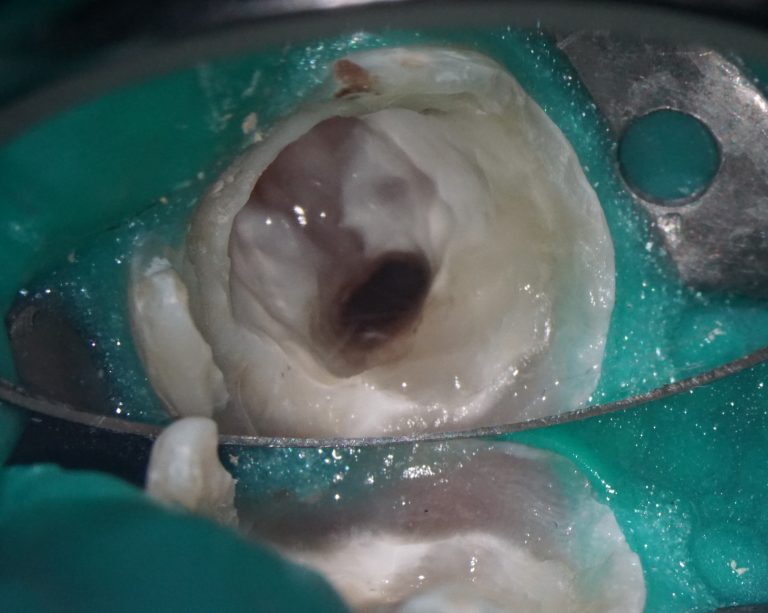

In this clinical case, the surgeon was tasked with correcting the pink aesthetics of the patient prior to the start of prosthetic treatment. Let’s explore how a clinician can leverage the capabilities of Diagnocat in such situations